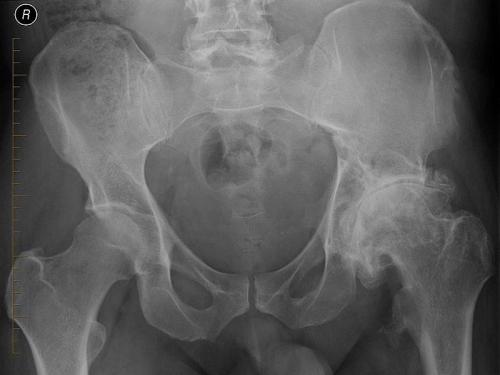

Слева направо — ухудшение состояния суставов по причине заболевания.

Деформирующий остеоартроз левого ТБС. Обратите внимание, как изменились очертания левого суставного сочленения по сравнению с правым.